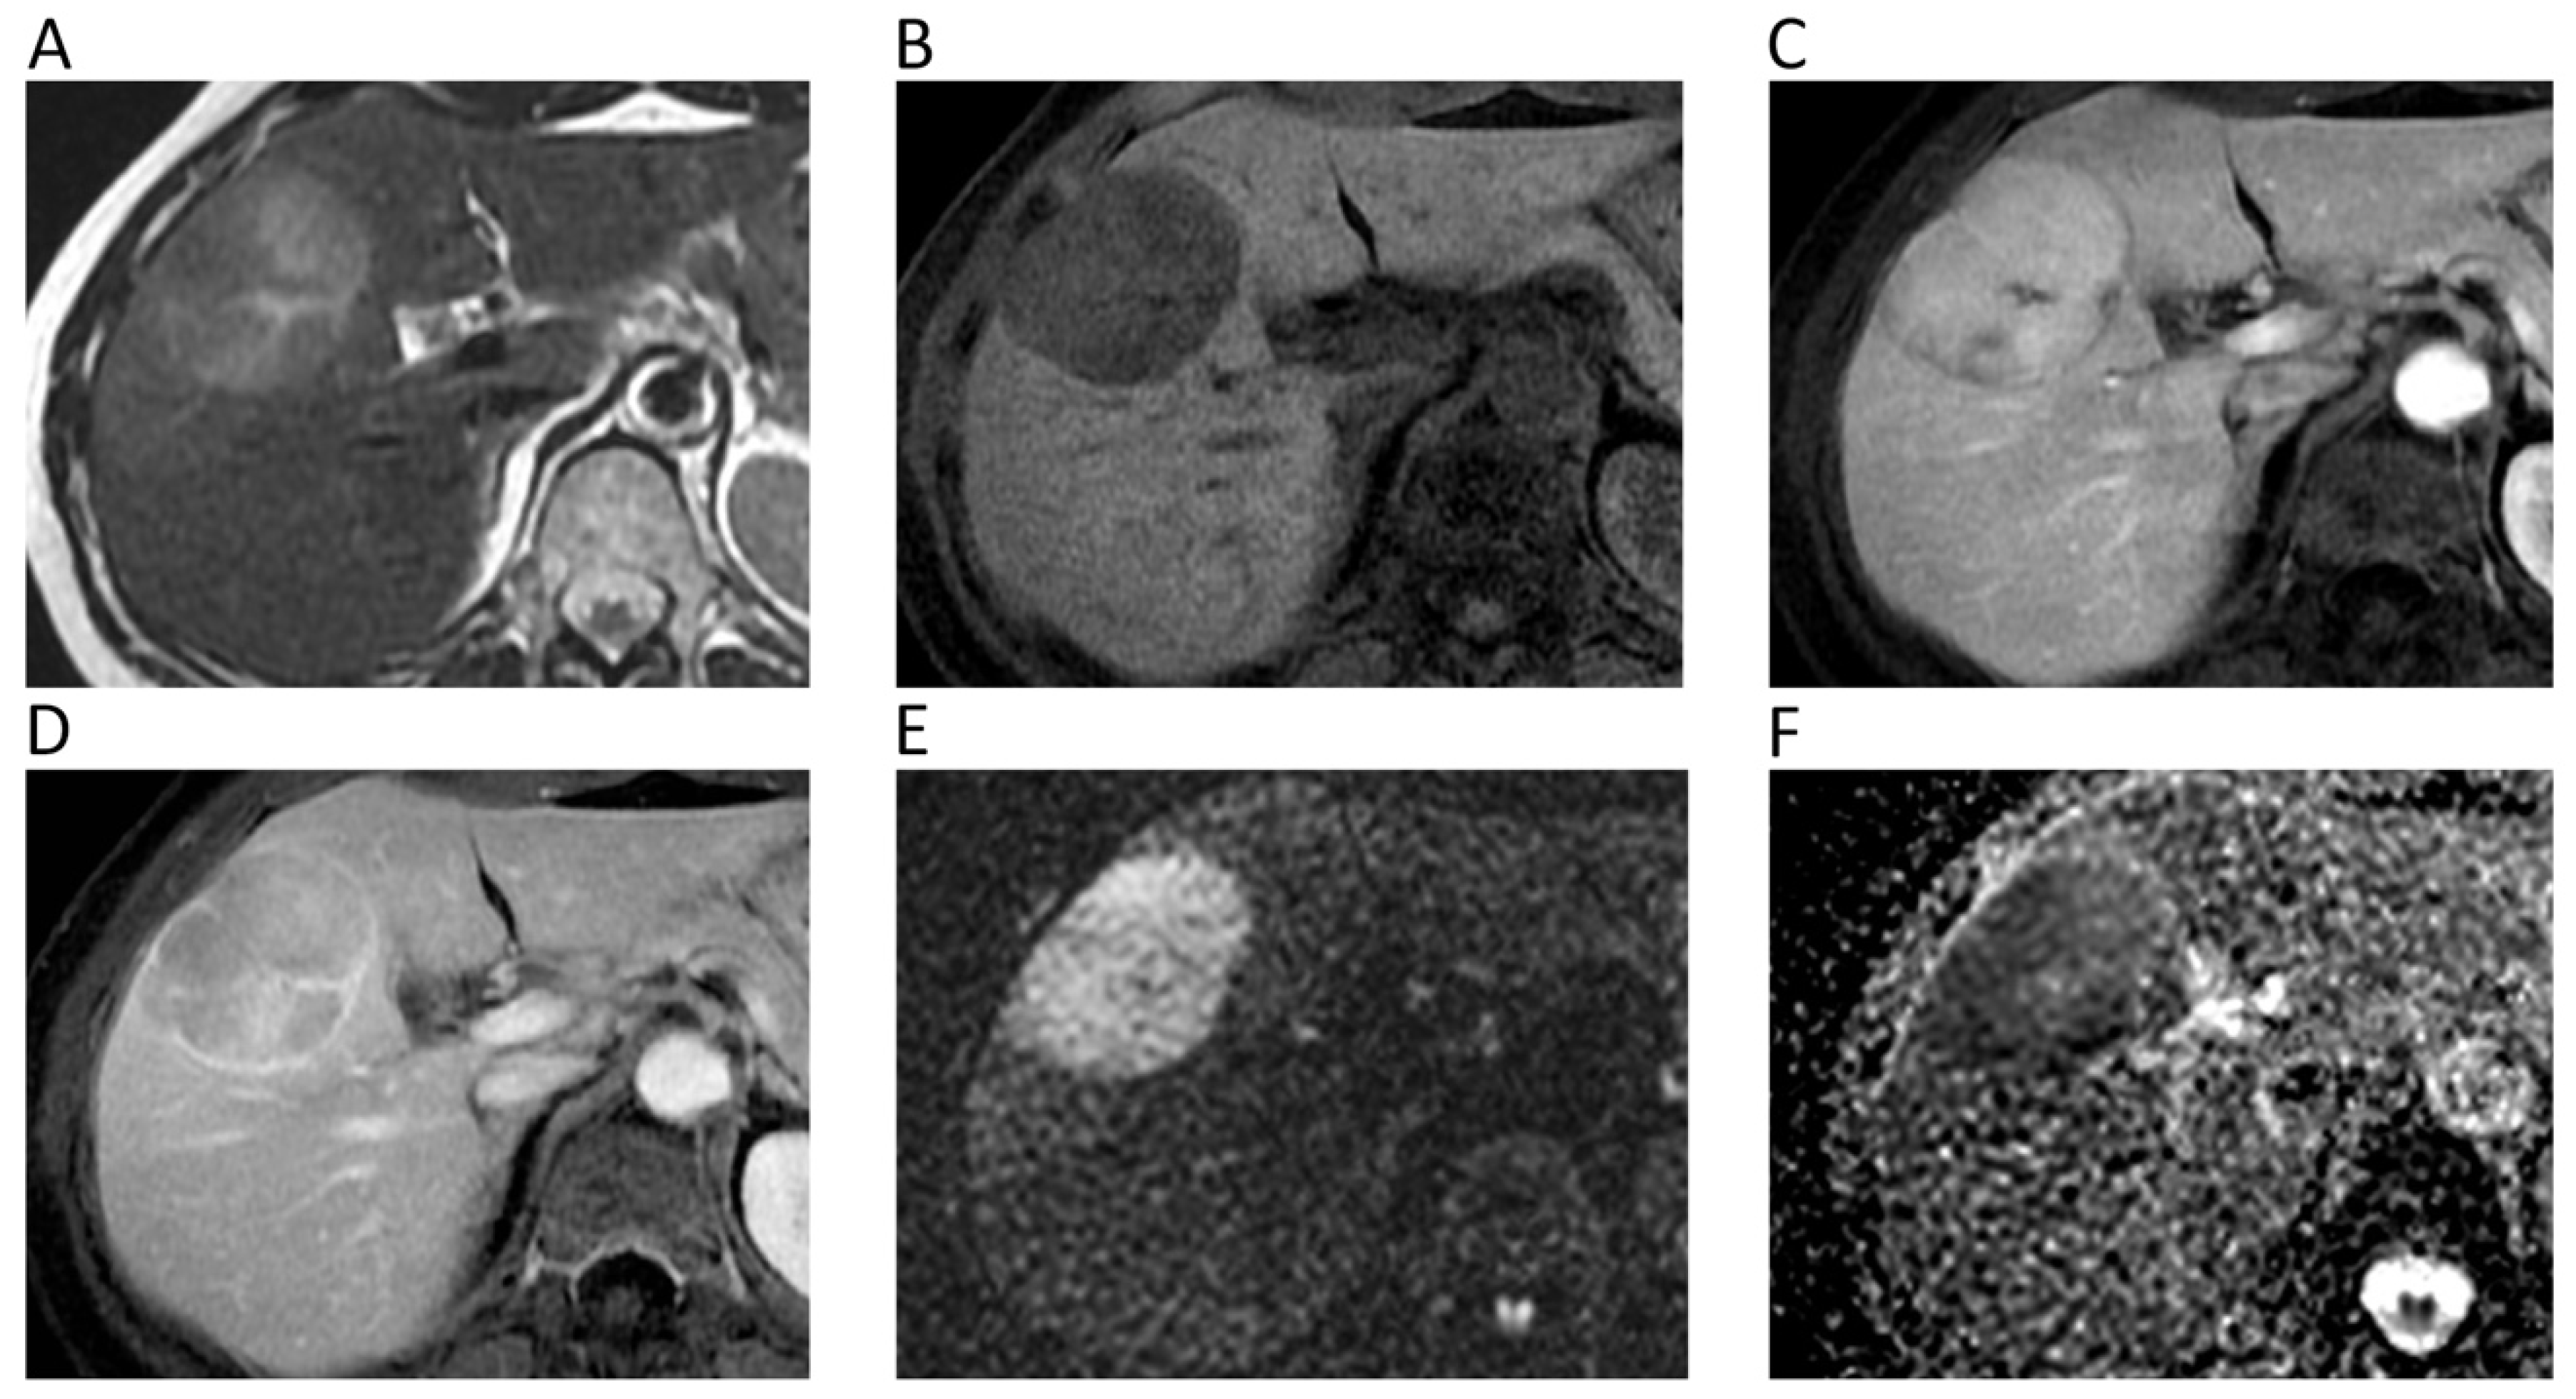

The role of DWI in liver imaging has been extensively investigated. The most used DWI sequence for liver imaging, nowadays included in routine liver protocol, is single-shot spin-echo fat-suppressed echo-planar imaging with at least three or four b-values, generally with the highest being b = 600. Compared to T2-weighted, DWI is superior in the diagnostic work-up of focal liver lesions, showing better performance in terms of detection rate and sensitivity even for small lesions (1–3 cm), which may be otherwise missed or misinterpreted [30]. DWI is considered reliable for detection and monitoring of liver metastases, especially those from neuroendocrine tumors, which are highly-cellulated, thereby being easily recognized in DWI [31].

ADCs from 1.5 to 1.6 × 10−3 mm2/s have been reported as cut-offs to identify malignant liver lesions [32]. However, a consensus is still lacking about the optimal ADC cut-off due to overlap between benign and malignant ones. As a general rule, signal hyperintensity on higher b-value DWIs with low ADCs are associated to malignant highly-cellulated and inflammatory (i.e., abscesses) lesions due to diffusion restriction (Figure 5) [32].

Figure 5.

Liver MRI of a 54-year-old female patient with histologically proven hepatocellular carcinoma (HCC) on her healthy liver. Axial T2w (A) and pre-contrast fat-suppressed 3D-gradient-echo T1w (B) images show a large mass with strong contrast enhancement on the arterial phase (C), wash-out and rim enhancement on the portal phase (D), high signal intensity on b = 800 DWI image (E), and low ADC values (mean ADC: 1.018 × 10−3 mm2/s) on the corresponding ADC map (F).

Currently, DWI is not included in the European Association for the Study of the Liver non-invasive diagnostic criteria for hepatocellular carcinoma (HCC). However, it has been shown that DWI increases sensitivity and positive predictive value (PPV) for the detection of HCCs < 20 mm thanks to better contrast-to-noise ratio and background suppression of normal parenchyma [33]. In addition, DWI has a promising role in anticipating HCC grading and distinguishing poorly from well/moderately differentiated HCC [34]. Furthermore, indeterminate hypovascular lesions with diffusion restriction in cirrhosis are often prone to develop hypervascularity and overt imaging features of HCC, making DWI a strong predictor for progression to hypervascular HCC [35]. A typical DWI finding of cholangiocarcinoma is the target sign, which is encountered in the hepatobiliary phase too. This imaging feature can be helpful to differentiate cholangiocarcinoma from HCC, being observed in about 87% and 15% of cases, respectively [36]. DWI can be an additional tool also to differentiate benign and malignant gallbladder lesions. Specifically, a recent meta-analysis including 557 patients has shown higher accuracy of qualitative assessment when compared with quantitative analysis of DW images (94% vs. 88%), especially when using 3T and thinner slices (≤5 mm) [37].